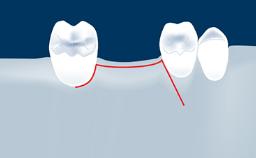

In this short microlearning module on digitally guided sinus floor elevation, we delve into a specialized aspect of the digital workflow for implant-guided surgery, focusing on the use of digital guides in the sinus floor elevation technique.

• define the manufacturing process of digital guides for SFE

• explore the intraoperative use of digital guides in SFE